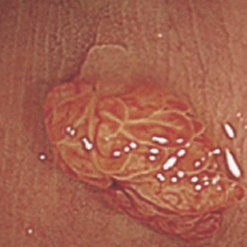

| 대장내시경 검사 |

대장내시경은 내시경을 이용해 대장 전체의 점막을 직접 관찰하여 용종, 염증, 출혈, 종양 등 다양한 대장 질환을 진단하는 검사입니다. 병변을 발견하게 되면 조직검사를 하게 되거나, 용종절제술을 할 수 있습니다. 특히 용종 중 선종(Tublur adenoma), 목 없는 톱니 병변(sessile serrated lesion), 전통 톱니선종(traditional serrated adenoma)은 그대로 두면 대장암으로 진행될 가능성이 높습니다.